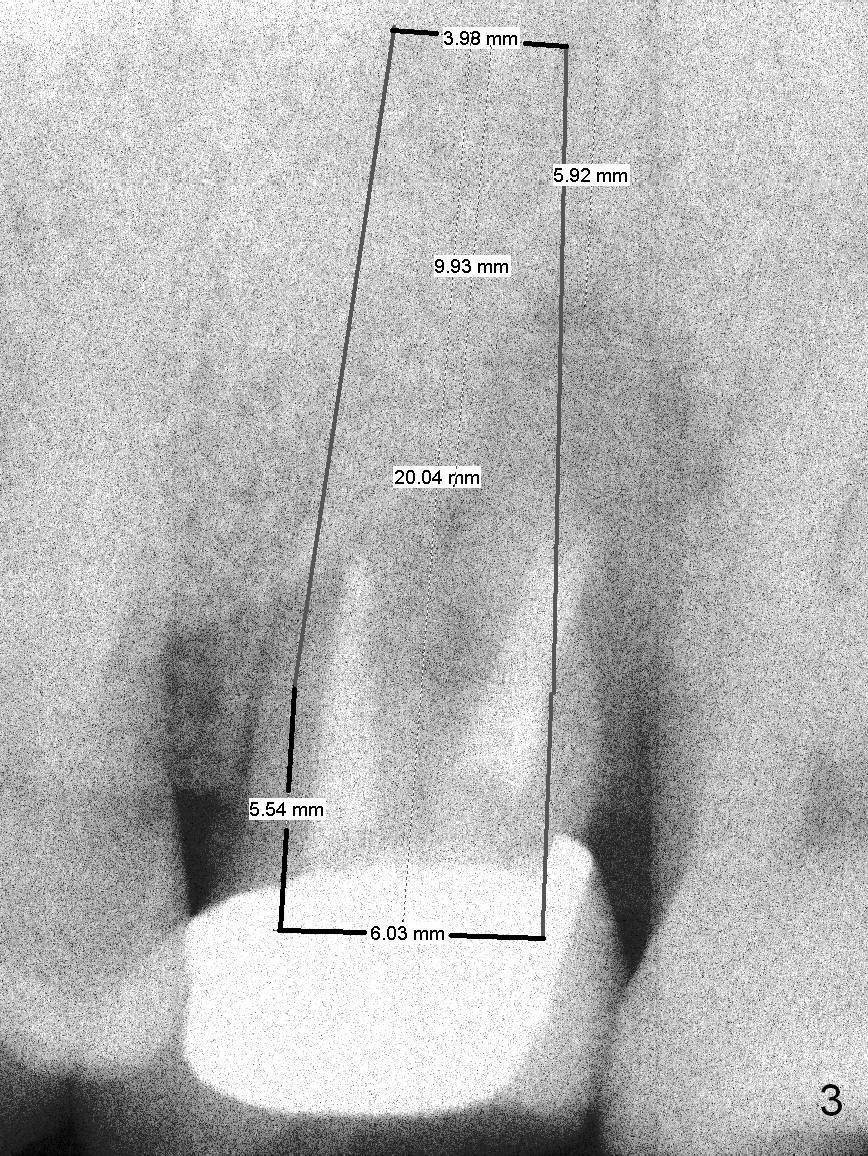

A 47-year-old man (LW) agrees to have the tooth #15 (Fig.1) extracted for implant after 4-year delay (Fig.2).  A 20 mm long implant will have at least 6 mm native bone for stabilization (Fig.3).  Bone density seems to be high.  Use Bicon drill and reamers until 3.5 mm, followed by 5x20 mm Tatum tapered tap and PA.

Also prepare UF implant system, since it is easier to clean cement in the posterior area than Tatum implant.  It is expected to place 5 or 5.5x16 or 18 mm UF implant.  Too large an implant may cause bone necrosis and bone loss.